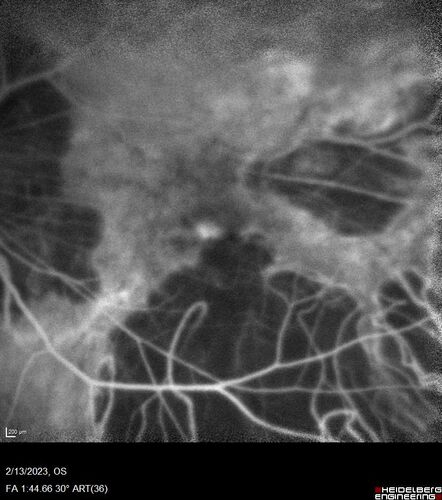

Myopic CNVM Left Eye

80 year old female. VA dropped to 20/125 but improved back up to 20/50 with Vabysmo

Myopic CNVM - Colobomas